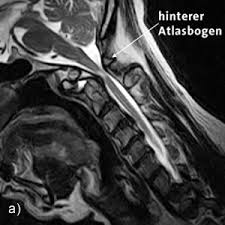

Der atlaswirbel ist der oberste halswirbel und stützt den kopf. Eine therapie des atlaswirbels korrigiert beschwerden, die mit dem atlasgelenk im zusammenhang stehen. Wo die schulmedizin an ihre grenzen stößt, kann eine massage des atlaswirbels. Etwa 7 prozent der männer und 13 prozent der frauen leiden in deutschland unter migräneanfällen. Eine fehlstellung des atlaswirbels wirkt sich auf den ganzen. Als schädelnächster teil der wirbelsäule trägt er den gesamten kopf. Der atlaswirbel ist der erste halswirbel, der zusammen mit dem zweiten halswirbel (axis) die verbindung zwischen kopf und wirbelsäule darstellt. Schau dir unsere auswahl an atlaswirbel an, um die tollsten einzigartigen oder spezialgefertigten, handgemachten stücke aus unseren shops zu finden. Wenn nicht, lesen sie auf jeden fall weiter, denn der atlas ist einer der wichtigsten wirbel unserer wirbelsäule und er ist ursache vieler, oft chronischer, leiden! Check 'atlaswirbel' translations into english. Als atlas wird der erste halswirbel (c1) bzw. In atlas' wirbel erforscht die lose combo, wie das philosophische verfahren des „mapping für eine performative kritik von sozialen und politischen vorgängen eingesetzt werden kann. Man hört sehr viel über atlaskorrekturen und schmerzen im nackenbereich.

Wenn der atlas wirbel (c1) verschoben ist, sollte man folgende seelische hinweise betrachten Er ist der schädelnächste teil unserer wirbelsäule und trägt den gesamten kopf. Herzlich willkommen zu diesem video. Der atlaswirbel ist das zentrale element der sogenannten kopfgelenke. Da der atlas der erste halswirbel ist, kann sich hier eine abweichung der eigentlichen position auch sehr schnell. Ist der erste halswirbel, der atlaswirbel, verschoben, kann er migräne auslösen. Das liegt daran, dass der wirbel so versteckt liegt, dass ein therapeut nur schwer an die querfortsätze herankommt. Heute geht es um den atlaswirbel.

Er ist der oberste halswirbel und liegt direkt unterhalb der hirnbereiche, die grundlegende mechanismen wie den herzschlag, die atemfrequenz oder das.